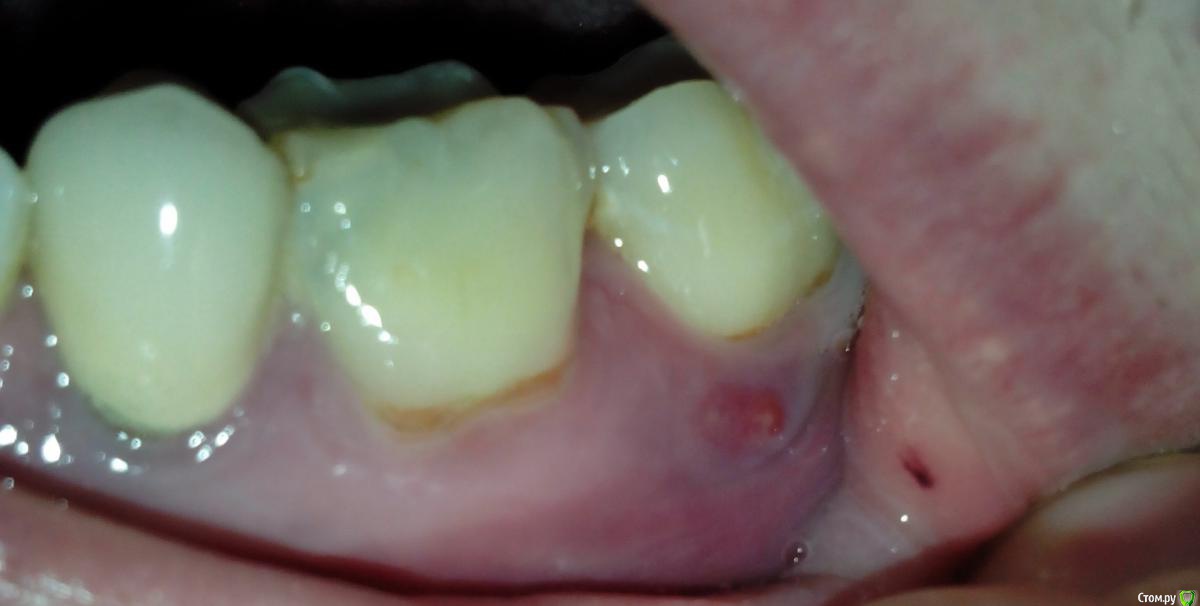

Чебурек Опубликовано 5 ноября, 2015 Поделиться Опубликовано 5 ноября, 2015 (изменено) Вылез свищ снизу слева под 37 зубом(на рентгене посередине). Три недели идет гной. Болей нет. Врач говорит что 36 зуб(на рентгене слева) тоже выглядит не молодцом. Подскажите как действовать. Изменено 5 ноября, 2015 пользователем Чебурек Ссылка на комментарий

IvanK Опубликовано 5 ноября, 2015 Поделиться Опубликовано 5 ноября, 2015 Лечение 36Восстановление контактного пункта 36, 37 Ищите терапевта 3 Ссылка на комментарий